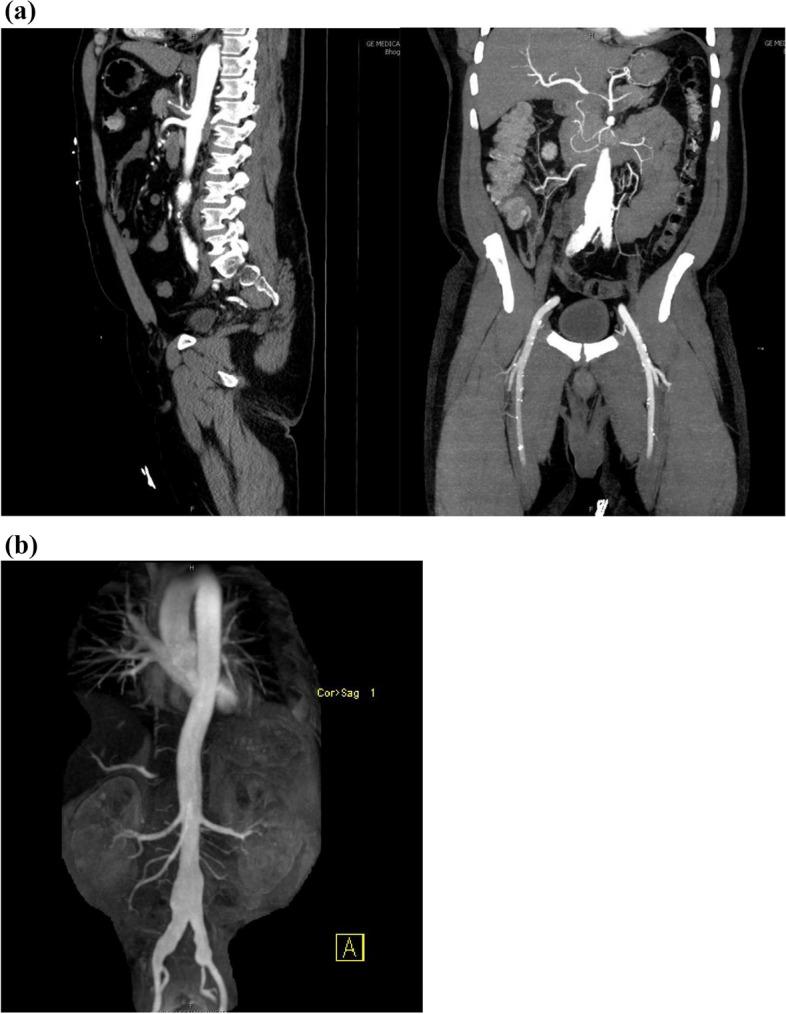

结节性多动脉炎(PAN)是一种系统性血管炎(SV),历史上被认为不会累及冠状动脉。冠状动脉造影和现代影像学显示冠状动脉狭窄和扩张,这与显著的发病率和死亡率相关。PAN 中的冠状动脉受到全身炎症引起的加速动脉粥样硬化的影响,这增加了固有动脉炎过程的风险。传统的动脉粥样硬化危险因素无法准确估计风险。很少有报道描述冠状动脉的病理变化,最佳治疗方法也受到限制。

冠状动脉受累的严重程度难以通过实验室监测来评估,但冠状动脉疾病与几种临床症状相关。弗雷明汉危险因素不能充分估计疾病负担。要将动脉粥样硬化与动脉炎分开,需要先进的血管造影方法。治疗包括抗凝、免疫抑制和血运重建。经皮冠状动脉介入治疗(PCI)一直是主要的治疗方法,尽管支架置入后由于管腔直径的不规则变化和新生内膜形成的报告,支架的应用受到限制。

当移植物选择避开 SV 的血管区域时,冠状动脉旁路移植术(CABG)提供了明确的治疗方法。除了回顾、更新和讨论文献外,我们还报告了一种新型的 CABG 构型。越来越多的证据表明,特定的临床症状提示存在冠状动脉受累。